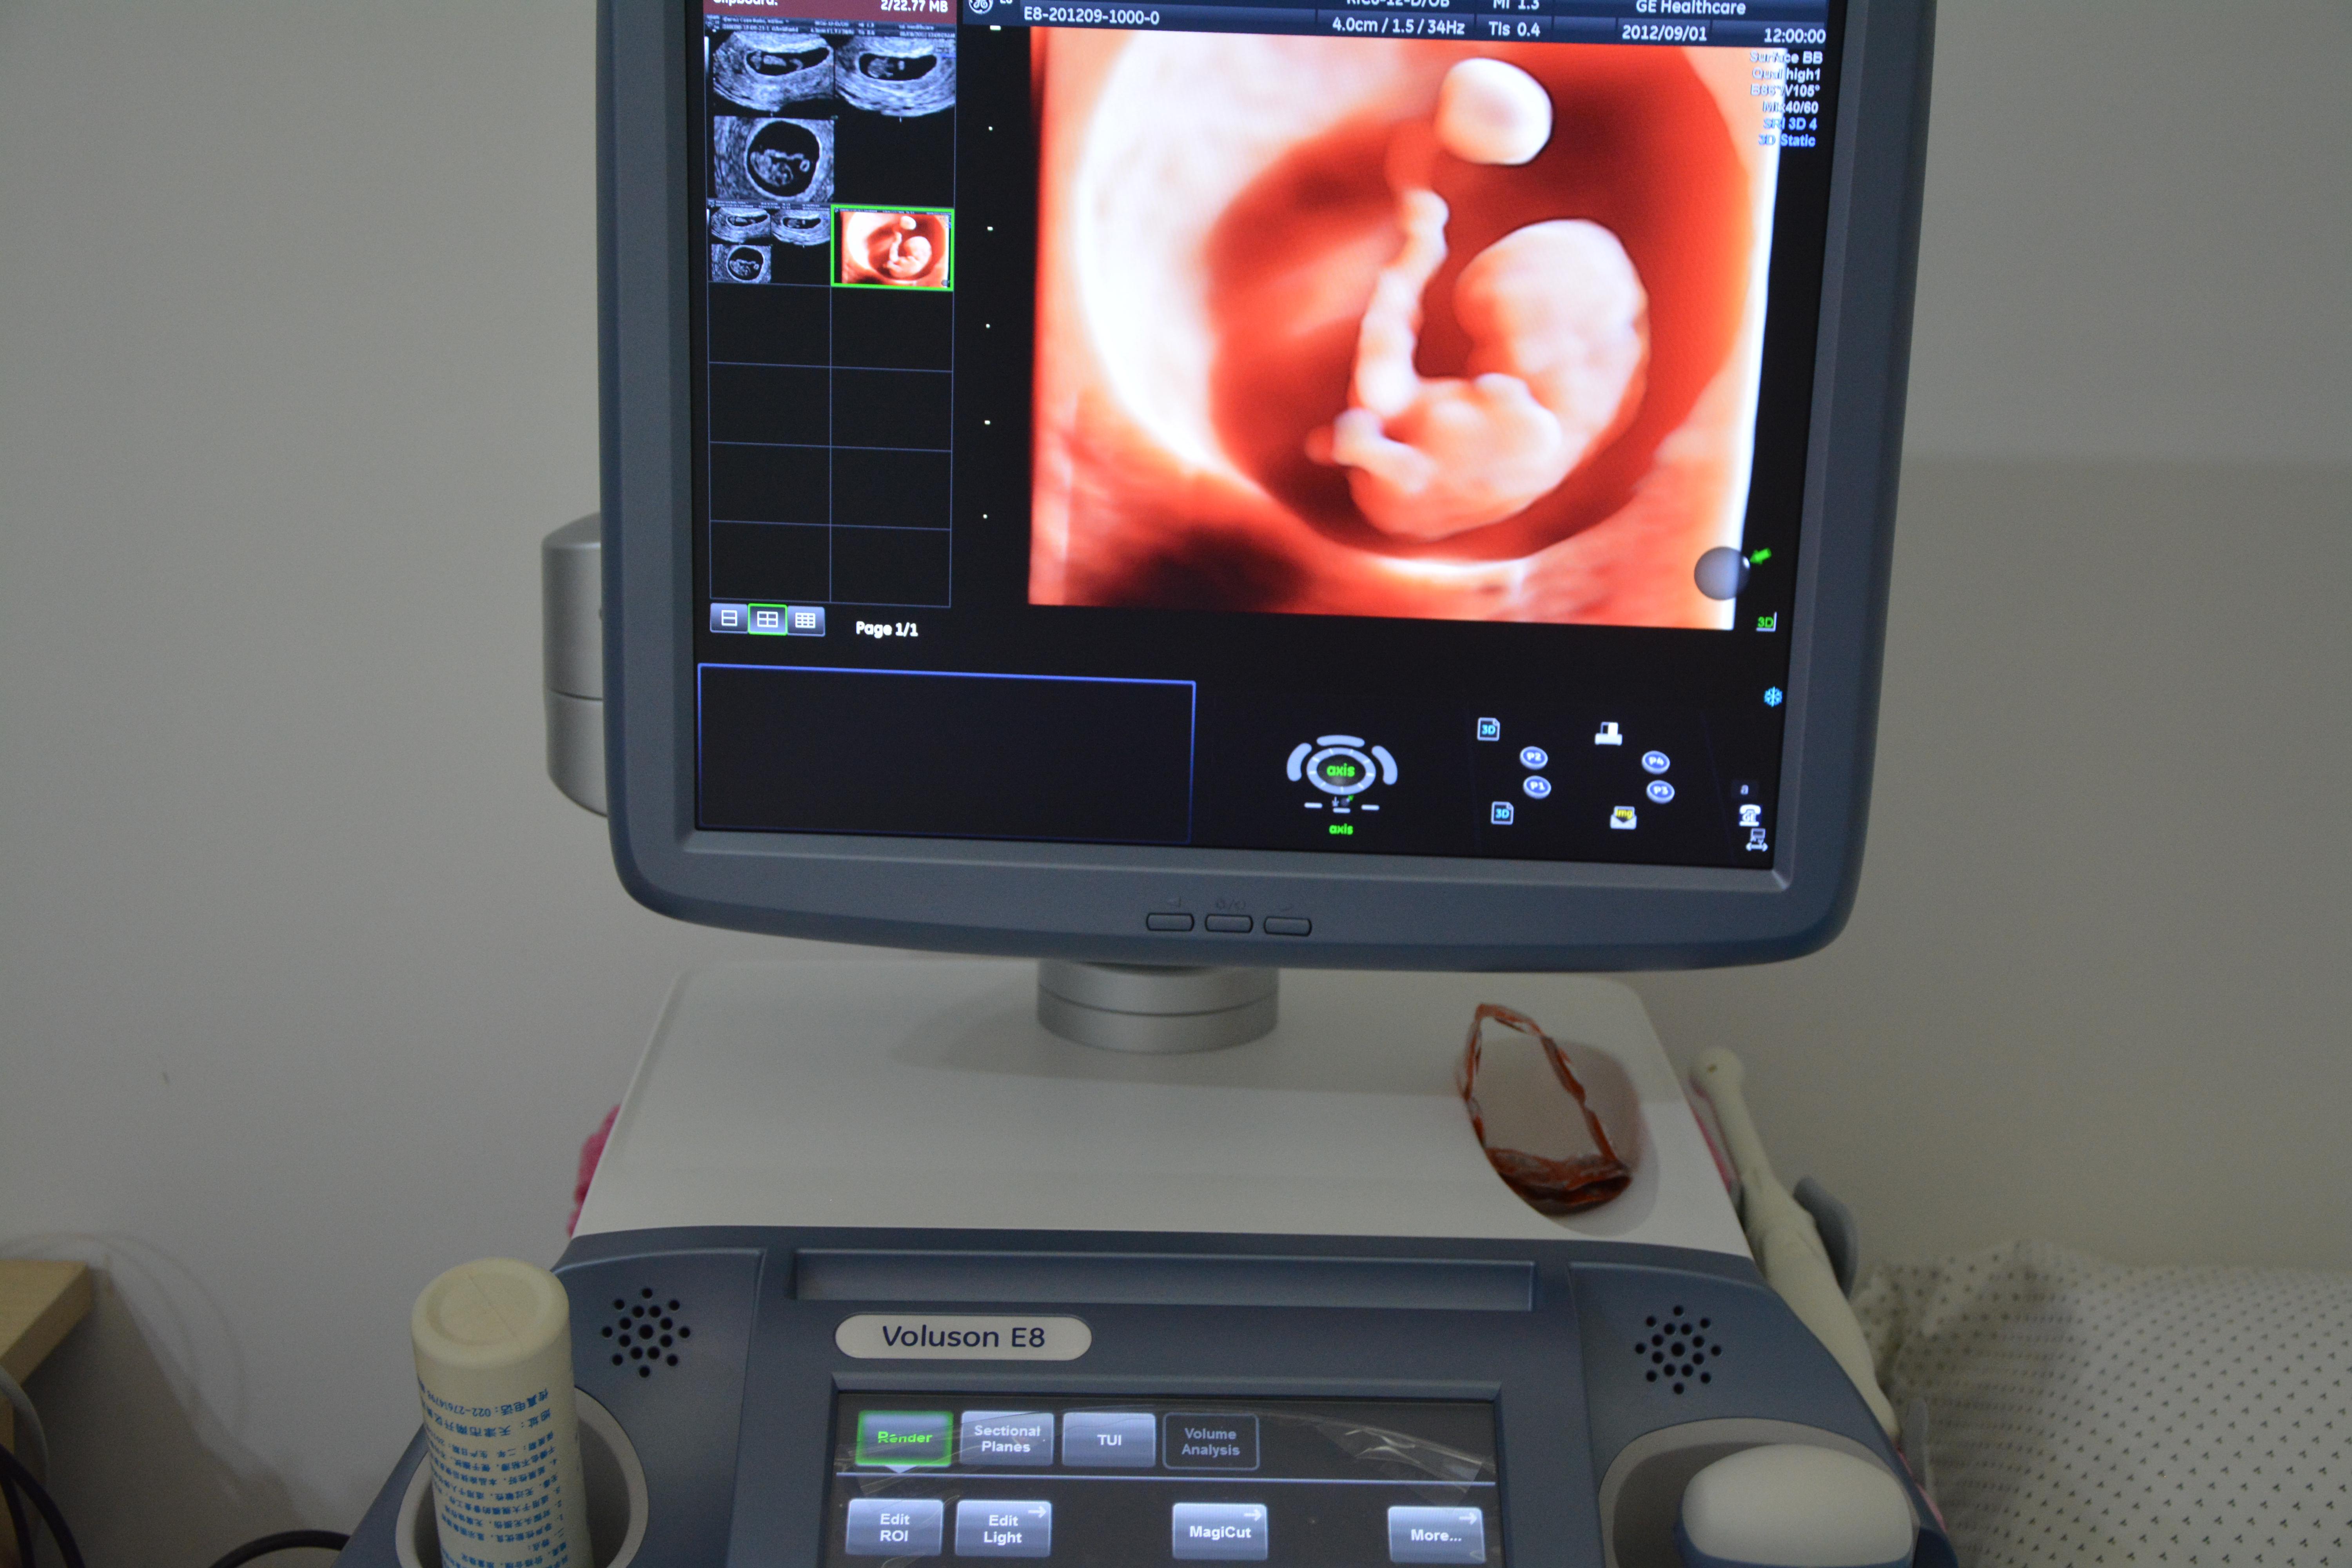

准妈妈一般在12周建档后,医院都会发一份定期产检的单子,写明白什么时间要进行什么样的检查。相信大家最感兴趣的应该就是孕25周后的四维彩超检查。现在的四维彩超技术,不仅能够清晰反应胎儿的样子,在子宫内的活动,医院还会贴心地给父母们拍摄宝宝的第一张彩色照片——四维彩超单。

四维彩超就像我们平时看的3D电影一样,让医生看到子宫内胎儿更为直观、立体的影像。大部分的胎儿四维照显得很丑,或者嘴巴大鼻子大,原因有以下三点。